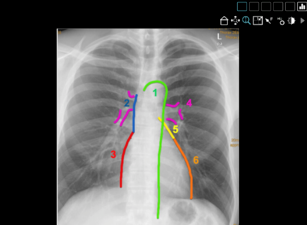

Für die Nutzung der CoRad-19-Kurse bedarf es keiner extra Software: Ein PC mit einer Internetverbindung reicht aus, um mittels der interaktiven fallbasierten Lehrmodule neues Wissen zu erwerben, es praxisnah anzuwenden und zu erweitern. Von Neuroradiologie über Muskuloskelettale Radiologie bis hin zur Interventionellen Radiologie decken die zehn Kurse aus dem CoRad-19-Angebot das gesamte Themenspektrum der radiologischen Ausbildung ab. Die Kursinhalte und Fallsammlungen wurden von sieben Experten aufgearbeitet: Dr. Saif Afat (Tübingen), Priv.-Doz. Dr. Bettina Baeßler (Zürich), Dr. Nienke Hansen (Köln), Dr. Katharina Müller-Peltzer (Freiburg), Priv.-Doz. Dr. Ahmed Othman (Tübingen), Dr. Daniel Pinto dos Santos (Köln), Dr. Fabian Rengier (Heidelberg).

CoRad-19 knüpft direkt an das bereits erfolgreich in conrad implementierte DRG-Angebot für die digitale Lehre an. Bereits seit 2018 stehen mit dem unirad-Projekt umfangreiche und interaktive Kurse für Medizinstudierende bereit, die individuell an die jeweiligen universitätsmedizinischen Fakultäten angepasst werden können. Von der Online-PACS-Workstation, wichtigen Krankheitsbildern, über fallbasierte MC-Fragen bis hin zu einem fallbasierten Nachschlagewerk: Die Inhalte sind didaktisch passend auf die Zielgruppe zugeschnitten. Jede Universität, die einen unirad-Kooperationsvertrag eingeht, erhält ab sofort auch automatisch Zugriff auf die ergänzenden modularen Lehrinhalte von CoRad-19.